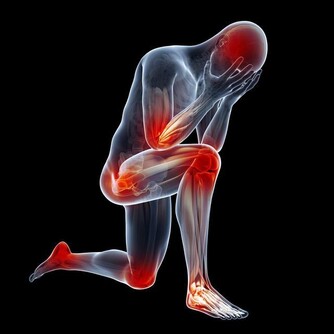

對青壯年和運動員而言,秋葵可消除疲勞、迅速恢復體力。